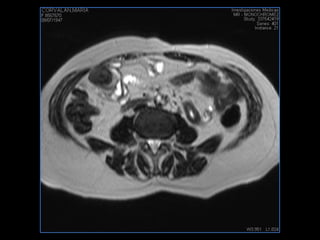

PROTOCOLO abdomen COR T2, AXIAL supresion grasa AX T1 +SAG T2  CON   GADOLINIO :  COR T1+AX T1(DIN) SAT: NO  FASE: RL THK: 6MM  COIL:  GAP: (FACTOR 1.4) 2MM FOV: 40 CM NEX:2 SINCRONIZACION RESPIRATORIA EN 3 O 4 CICLOS ALE

PROTOCOLO pelvis SAG T2, Y FAT SAT (FINOS) AXIAL T1  AX FAT SAT CON   GADOLINIO :  AX T1 Y COR T1 SAT: NO  FASE: RL THK: 3MM  COIL:  GAP: (FACTOR 1.4) 1MM FOV: 40 CM NEX:2 SINCRONIZACION RESPIRATORIA EN 3 O 4 CICLOS ALE